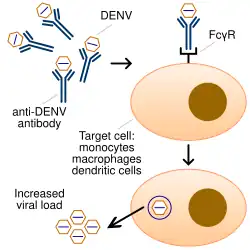

Chronic diseases – such as asthma, sickle cell anemia, and diabetes mellitus – increase the risk of developing a severe form of the disease.[44] Other risk factors for severe disease include female sex and high body mass index.[22][31] Infection with one serotype is thought to produce lifelong immunity to that type, but only short-term protection against the other three.[23] Subsequent re-infection with a different serotype increases the risk of severe complications due to a phenomenon known as antibody-dependent enhancement (ADE).[10][45]

The exact mechanism of ADE is not fully understood.[45] It appears that ADE occurs when the antibodies generated during an immune response recognize and bind to a pathogen, but they fail to neutralize it. Instead, the antibody-virus complex has an enhanced ability to bind to the Fcγ receptors of the target immune cells, enabling the virus to infect the cell and reproduce itself.[45][46]